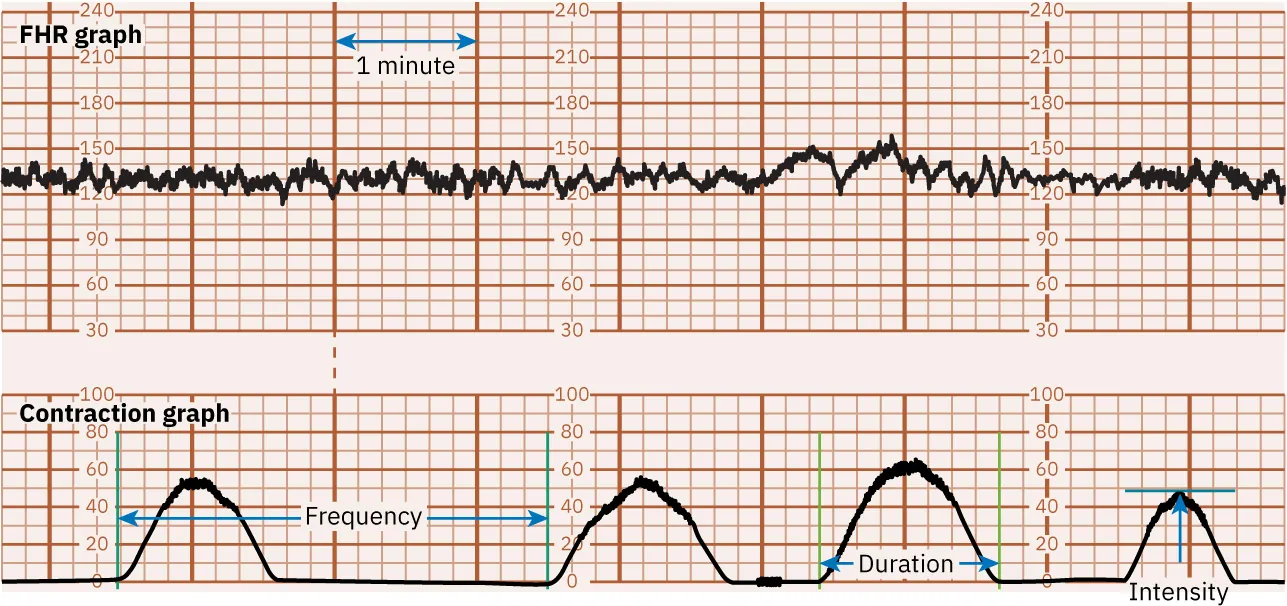

Uterine contractions are monitored for frequency, intensity, and duration. As discussed in Chapter 15 Process of Labor and Birth, the frequency is how many minutes from the start of one contraction to the start of the next contraction. Intensity is the strength of the contraction. Duration is the number of seconds from the start to the end of a contraction.

As shown in Figure 16.15, the monitor graph is divided by darker or more prominent vertical lines to represent 1 minute of time and less prominent vertical lines showing 10-second intervals. The upper set of horizontal lines represents the fetal heart rate in beats per minute (bpm), usually in intervals of 10 bpm. The lower set of horizontal lines represents the intensity of the contractions in millimeters (mm) of mercury (Hg), in intervals of 5 to 10 mm Hg.

An image showing a fetal heart rate and uterine contraction monitoring graph. The top graph represents the fetal heart rate with a line oscillating around 120 beats per minute, marked by regular vertical red lines. The bottom graph shows uterine contractions with three bell-shaped curves aligning with the red lines above, and green lines indicating the start and end of contractions.

Figure 16.15 Fetal Heart Rate and Contraction Monitor Graph This monitor tracing shows the fetal heart rate baseline of 130. The contraction frequency is 2 to 3 minutes. The contraction duration is 45 to 70 seconds. The contraction intensity is 50 to 70 mm Hg. (attribution: Copyright Rice University, OpenStax, under CC BY 4.0 license)